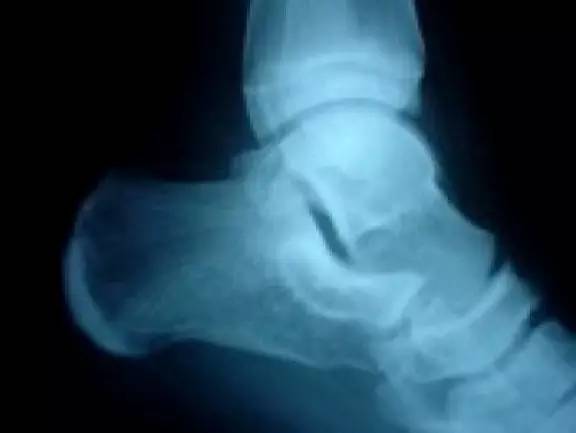

足踝部骨折

正常足踝(来源:OrthoInfo-AAOS)